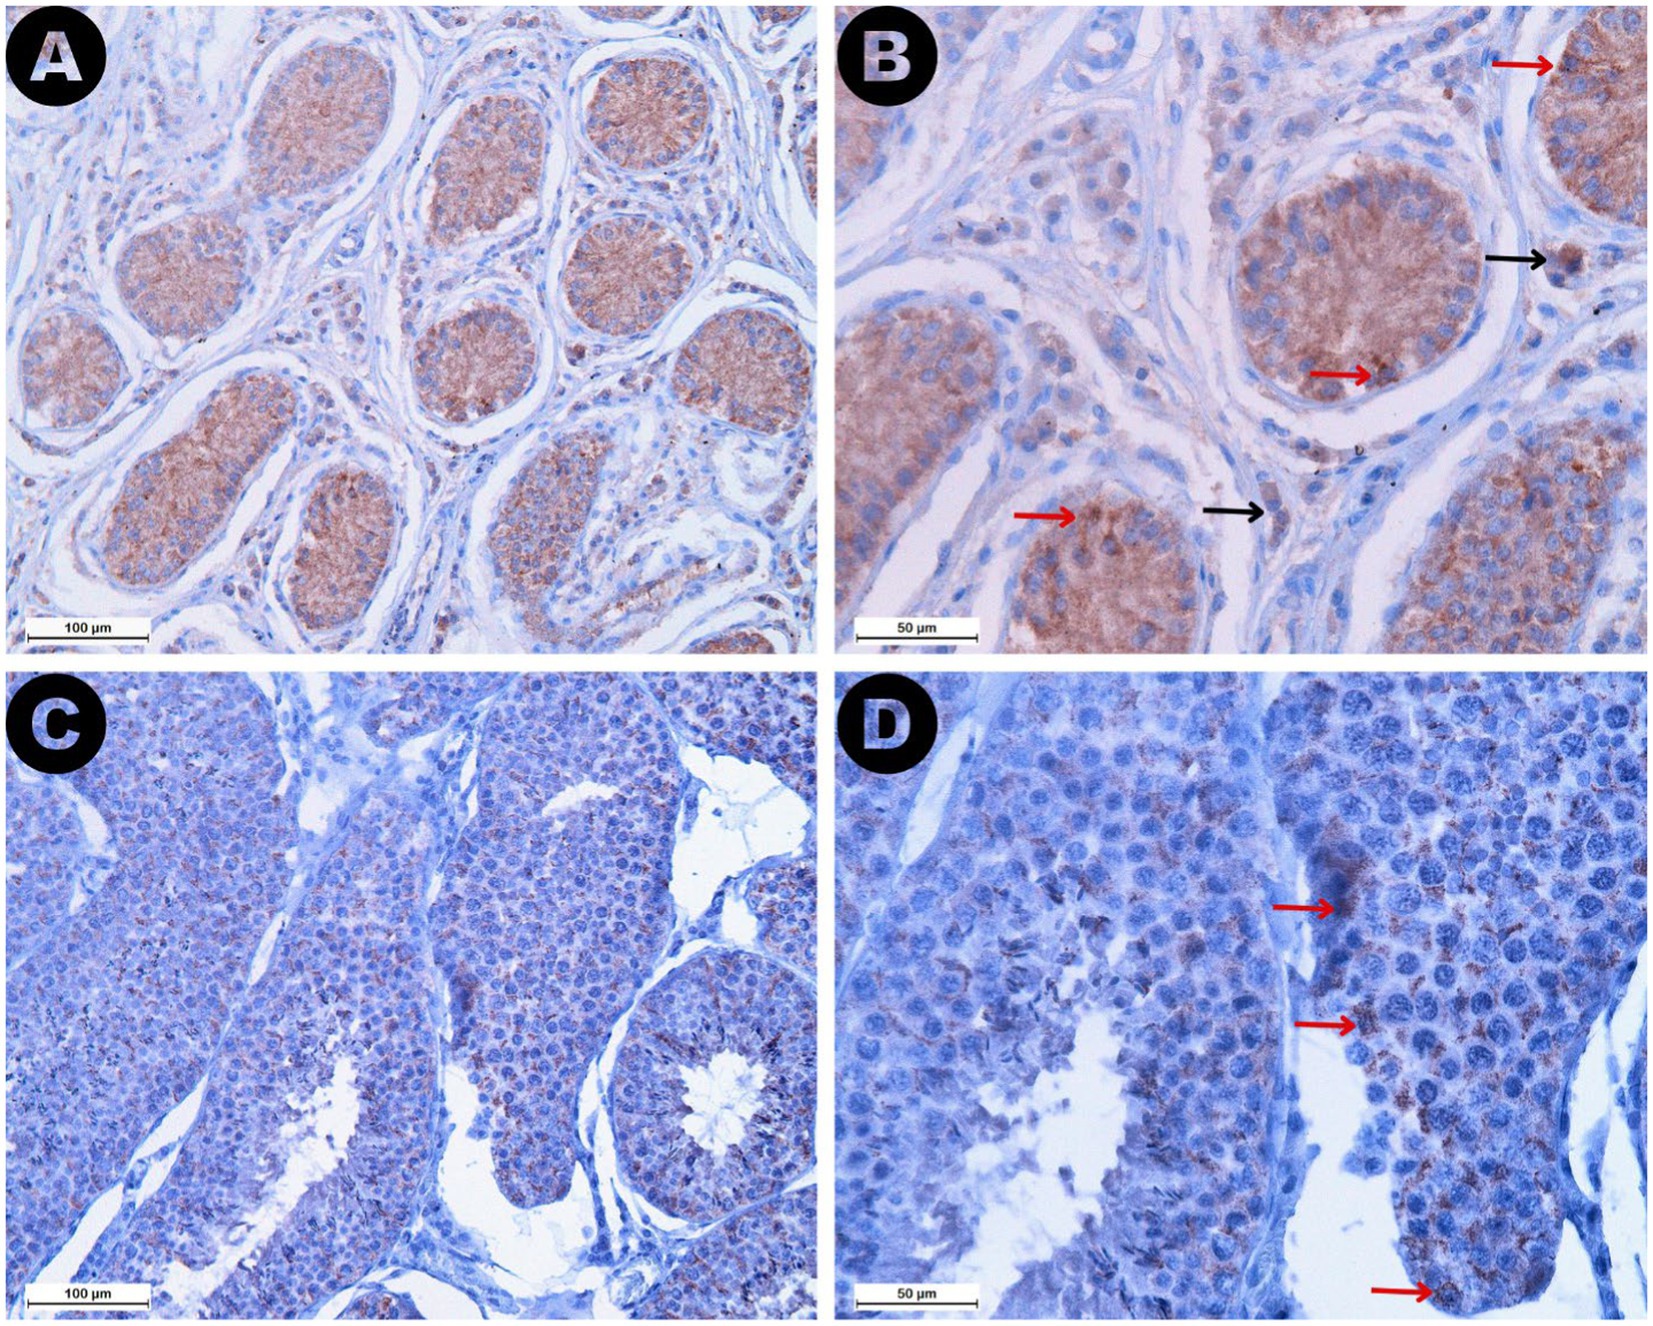

3.2.4 Cuantificación de la expresión tisular de AMH

La expresión de AMH se reveló como tinción marrón en ambos ROI (Figura 7). Se observó una mayor expresión de AMH en las células de Sertoli de los testículos retenidos, lo que resultó en niveles de expresión significativamente más altos en los túbulos seminíferos del grupo RET (mediana 32,42%, IQR = 15,11) en comparación con el grupo CONTRA (mediana 9,25%, IQR = 5,55, p ≤ 0,05) y el grupo DES (mediana 4,63%, IQR = 1,43, p ≤ 0,001). Sin embargo, la diferencia en la expresión de AMH entre los grupos CONTRA y DES no fue significativa (p = 0,444). La reactividad en el ROI del espacio intersticial fue menor que la expresión intratubular en todas las muestras (Z = −4,703, p < 0,001). Las comparaciones basadas en grupos mostraron que los valores de reactividad del espacio intersticial dentro de las muestras de DES (mediana 0,05%, IQR = 0,08) fueron más bajos en comparación con las muestras de RET (mediana 2,36%, IQR = 3,24, p ≤ 0,001), pero no difirieron significativamente de las muestras de CONTRA (mediana 0,12%, IQR = 0,15, p = 1,000). Además, los niveles de expresión de AMH intratubular e intersticial no variaron sustancialmente entre los testículos retenidos inguinalmente (p = 1.000) y las gónadas retenidas abdominalmente (p = 1.000).

Curiosamente, los valores séricos de AMH se correlacionaron positivamente con la expresión de AMH tisular tanto en el espacio intersticial (ρ = 0,494, p ≤ 0,01) como en los túbulos seminíferos (ρ = 0,610, p ≤ 0,001). Por el contrario, los túbulos seminíferos más pequeños se asociaron con una mayor reactividad a la AMH en ambos ROI (túbulo seminífero: ρ = −0,774, p ≤ 0,001; espacio intersticial: ρ = −0,725, p ≤ 0,001). Del mismo modo, las puntuaciones de Johnsen disminuyeron a medida que aumentaba la expresión de AMH tisular en los dos compartimentos analizados (túbulo seminífero: ρ = −0,756, p ≤ 0,001; espacio intersticial: ρ = −0,679, p ≤ 0,001). Todas las correlaciones entre las variables analizadas se presentan brevemente en la Tabla 2.

De acuerdo con nuestros resultados, la expresión de AMH fue mayor en los túbulos seminíferos de los testículos retenidos en comparación con las gónadas descendidas, debido a que las células de Sertoli más reactivas de los testículos criptorquídeos fueron más reactivas. En otras palabras, la expresión tisular de AMH se intensificó en los túbulos comprimidos, mostrando pocas células germinales o solo células de Sertoli. Estos hallazgos se alinean con los datos publicados sobre sementales criptorquídeos y gatos en los que la tinción de AMH se correlacionó negativamente con las áreas de los túbulos seminíferos y las puntuaciones de Johnsen (29, 44). En perros, una mayor inmunotinción de AMH en los testículos retenidos también se explicó por la presencia de menos células germinales en los túbulos seminíferos, en comparación con las gónadas escrotales (31). Por lo tanto, la expresión tisular de AMH parece aumentar debido a cambios estructurales o funcionales dentro del testículo, asociados con la desdiferenciación o demaduración de las células de Sertoli, lo que lleva a niveles séricos elevados de AMH (14, 45). Los testículos de ratón gravemente dañados mostraron una mayor intensidad de tinción de AMH, identificando principalmente células de Sertoli reactivas, y correlacionándose con un mayor grado de apoptosis (12). En los testículos de hombres infértiles, la atrofia tubular se caracterizó por la coexpresión de AMH y CK-18 en las células de Sertoli (45). Este patrón de expresión fue específico para los túbulos que mostraron detención espermatogénica en la etapa de espermatogonia, así como en los túbulos que mostraron solo células de Sertoli (45), similares a nuestros túbulos 2 y 3 de la puntuación de Johnsen.

Inicialmente se pensó que el receptor AMH se localizaba exclusivamente en la membrana de las células de Sertoli, pero investigaciones posteriores también han identificado su presencia en las células de Leydig (46). Además, la interacción entre AMH y los receptores ubicados en las células de Leydig puede tener el potencial de inhibir la producción de testosterona (46). Curiosamente, en las muestras de testículos retenidas se observó una mayor reactividad en el espacio intersticial en comparación con el mismo compartimento de las gónadas descendidas, lo que sugiere una mayor interacción entre los receptores mencionados anteriormente y la AMH. Por lo tanto, podemos considerar que la AMH también podría reflejar la capacidad esteroidogénica del tejido testicular, que puede verse alterada por lesiones degenerativas como las observadas en sementales con degeneración testicular inducida térmicamente (47).